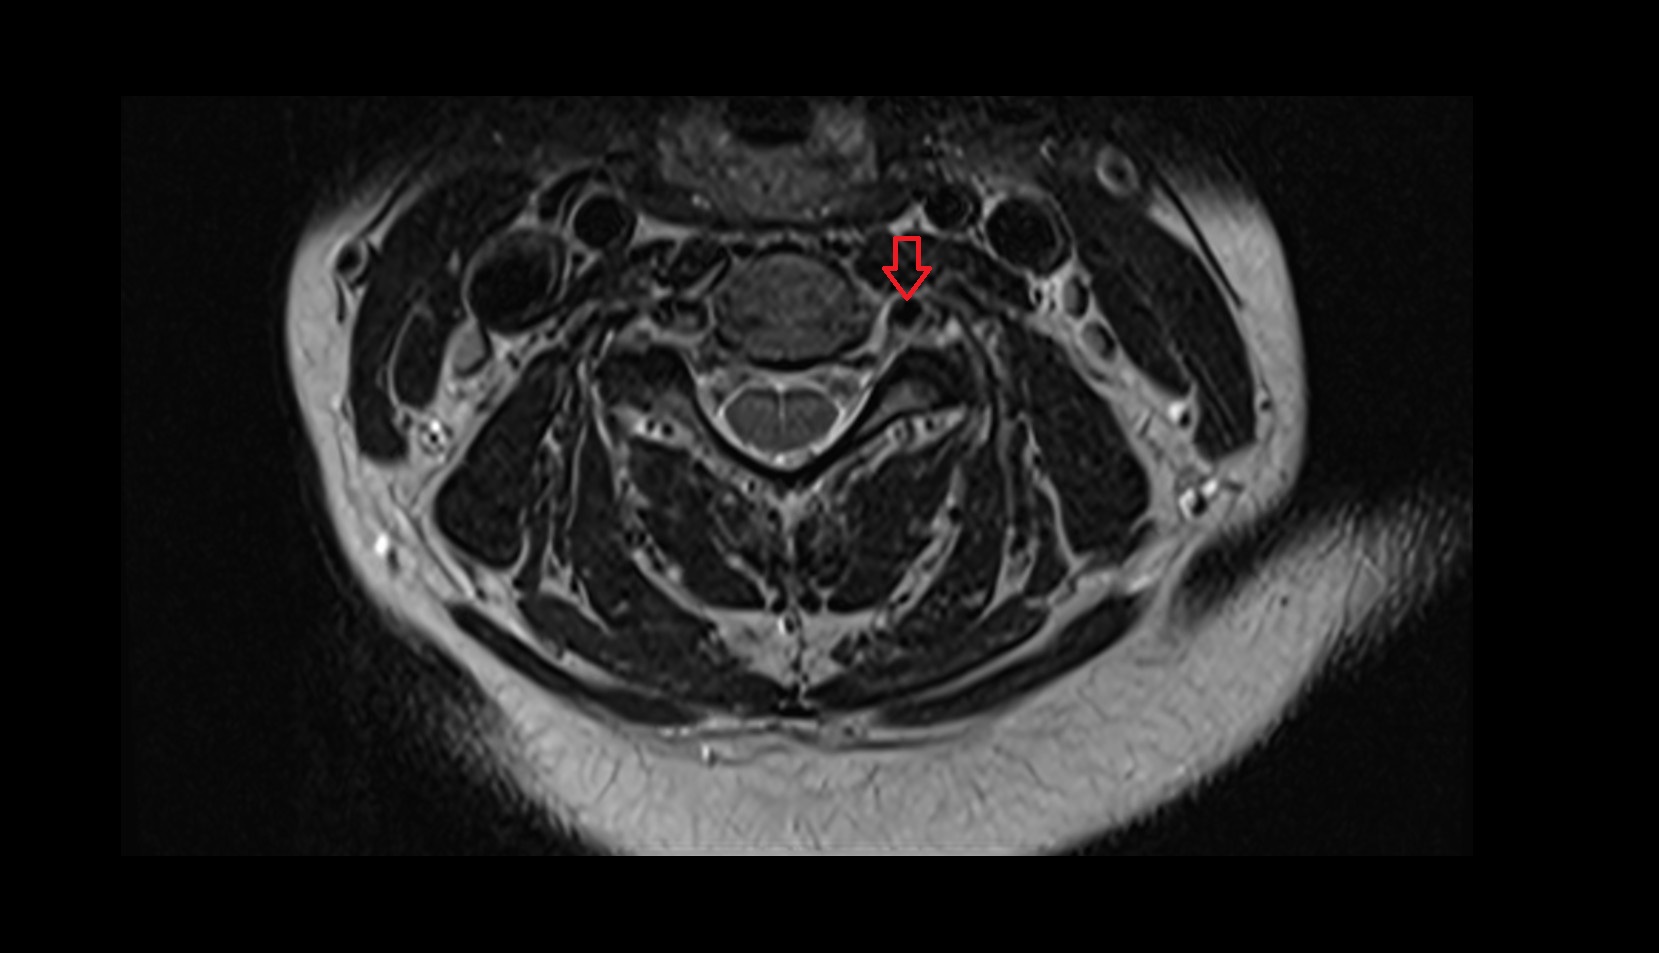

- Spinal cord

- Anulus fibrosus of intervertebral disc

- Nucleus pulposus of intervertebral disc

- Intervertebral Disc